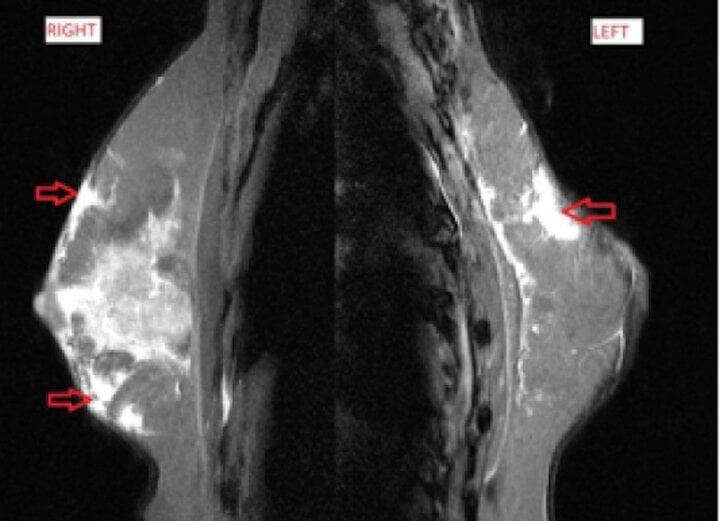

Tại viện, kết quả siêu âm và chụp cộng hưởng từ của bệnh nhân cho thấy, hình ảnh các ổ dịch viêm, áp xe rải rác tuyến vú hai bên. Đồng thời, bệnh nhân được chọc dịch ổ áp xe lấy mẫu bệnh phẩm xét nghiệm, kết quả dương tính với mycobacterium fortuitum - một dạng vi khuẩn lao không điển hình (NTM).

Hình ảnh chụp cộng hưởng từ của bệnh nhân cho thấy các ổ viêm, áp xe rải rác tuyến vú hai bên. (Ảnh: BVCC)